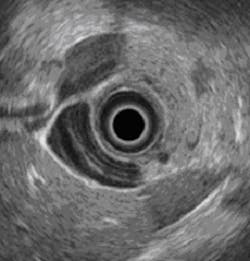

Dubbed "Sonopill", it has the potential to allow minimally-invasive diagnosis and even treatment of a range of gastrointestinal disorders. Patients would simply swallow the device, which would then transmit ultrasound images as it passed through the gastrointestinal tract.

The principal current method of examining problems within the gastrointestinal tract is endoscopy, which is very uncomfortable and requires a high-level of clinical skill.

"So-called 'pillcams' are a developing area of medical technology which have already benefitted more than one million patients. What we want to do is develop that technology further to include ultrasound, for the first time seeing beyond the surface of the gastrointestinal tract into the tissue itself," says Professor Cochran.